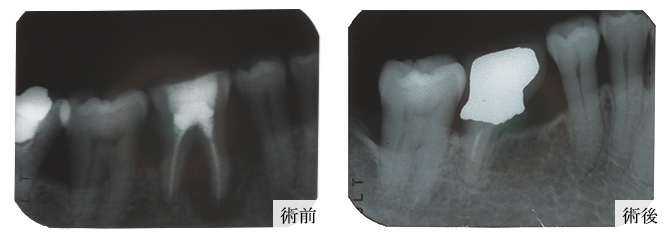

術前術後

エムドゲイイン症例01

歯周再生写真01